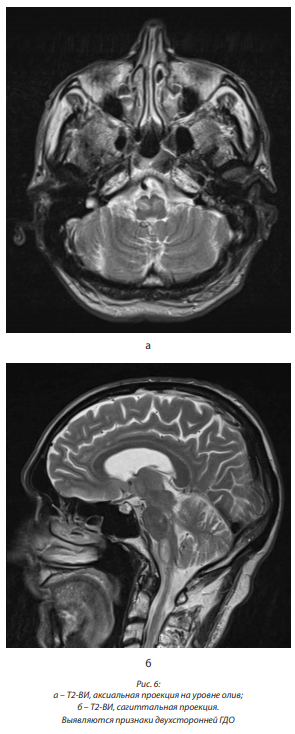

При МРА от октября 2012 г.: сужений, аневризм, патологической извитости магистральных артерий не выявлено; вариант отхождения левой задней мозговой артерии (ЗМА), сосудистая связь с каверномой отсутствует (рис. 2, а, б, в, г, д).

В сентябре 2013 г. МРТ головного мозга выявила симметричную, бивентрикулярную водянку; рубцово-глиозные изменения в области миндаликов мозжечка справа; отсутствие патологического накопления контрастного вещества, отсутствие расширения оболочечных пространств полушарий мозга; без динамики по сравнению с МРТ от декабря 2012 г. Не описаны имевшиеся признаки ГДО. МРА дополнительной сосудистой сети не выявила (рис. 4, а, б, в).

При МРТ головного мозга в сентябре 2016 г. выявлена умеренно выраженная компенсированная бивентрикулярная водянка; в проекции медиальных отделов правой гемисферы и червя мозжечка – зона постоперационных изменений размером 27×15×16 мм, со следами гемосидерина, правый выворот IV желудочка подтянут к зоне изменений, при контрастном усилении участков патологического накопления контрастного вещества не выявлено; атрофические изменения субкортикальных отделов обеих гемисфер мозжечка. Заключение: состояние после РТ ЗЧЯ справа, удаление каверномы червя мозжечка. Данных за рецидив не выявлено. Атрофические изменения субкортикальных отделов обеих гемисфер мозжечка (рис. 5, а, б, в).